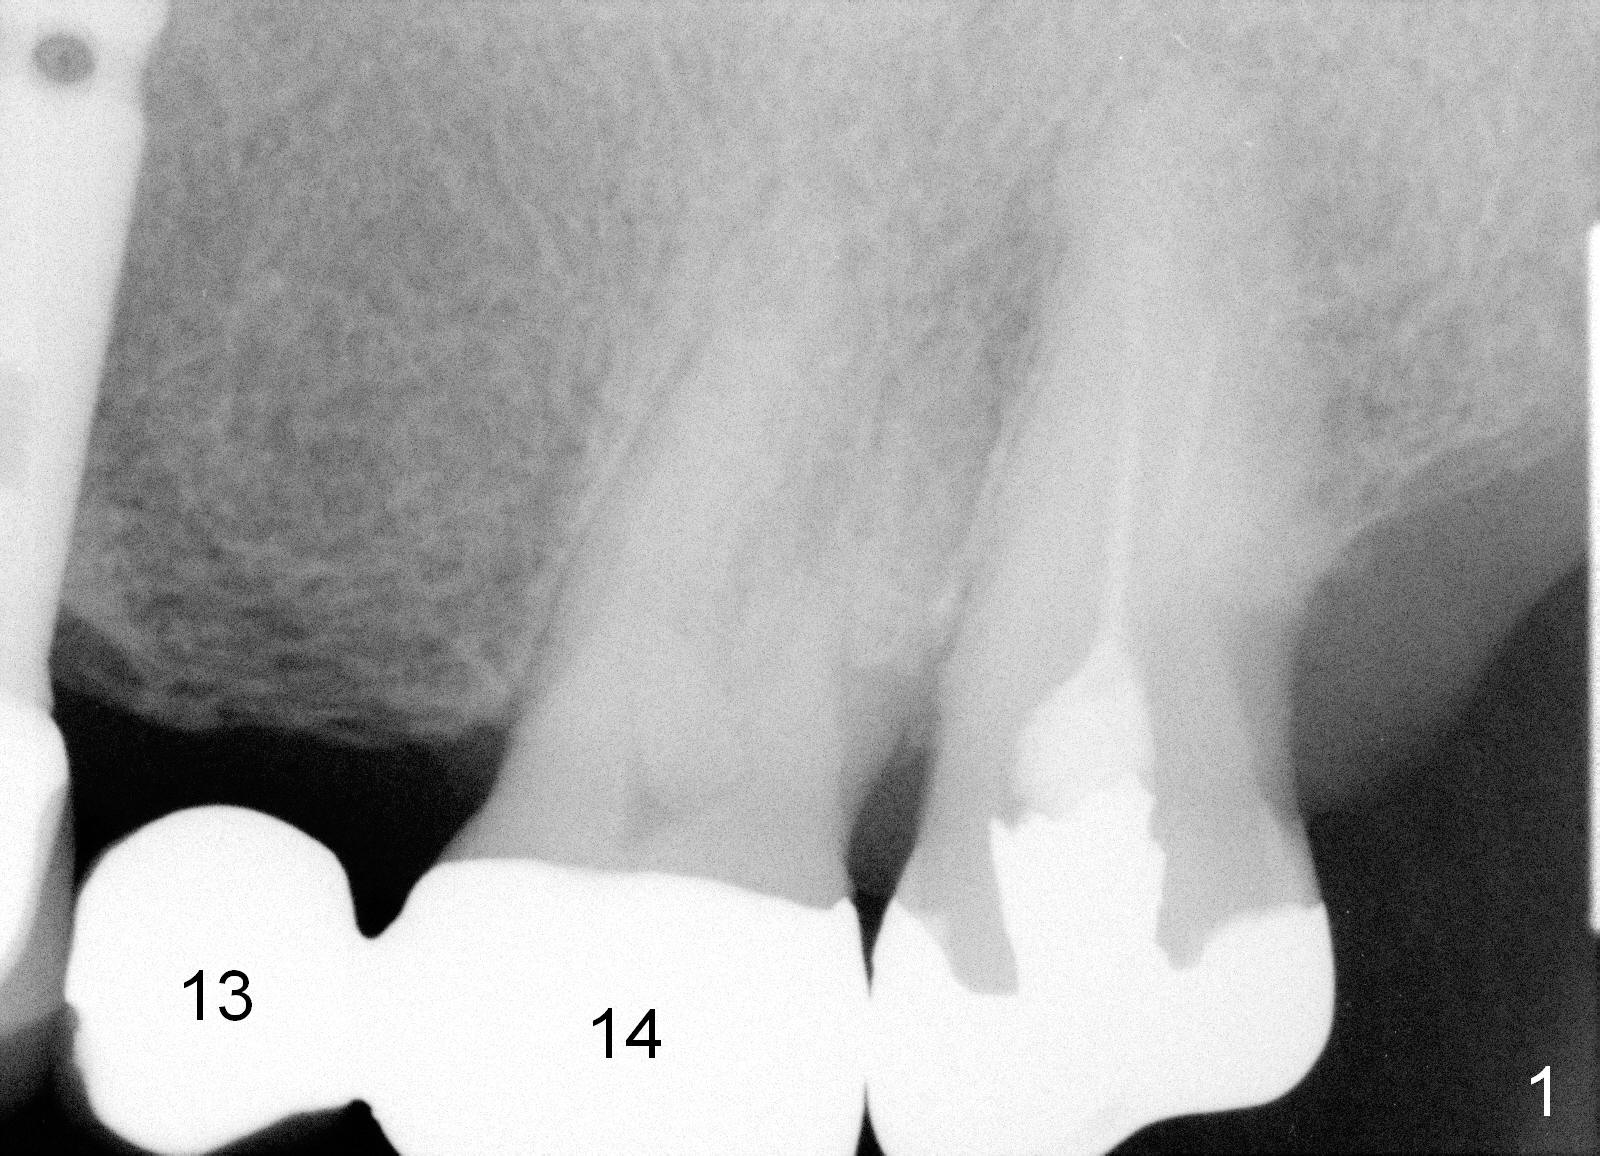

A 71-year-old man has multiple restorations, most of which are high noble crowns (Fig.0). He used to have a cantilever bridge involving the teeth #13 and 14 (Fig.1). It fractures (Fig.2,3). Considering the obliterated canals (Fig.1) and history of "bristle teeth", implants will be the best treatment option. The tooth #14 will be sectioned (Fig.3 upper left inset) for extraction. The osteotomy will be initiated in the septum slightly palatal, as shown by O in Fig.3 so that the immediate implant will be almost obliterating the socket mesiodistally (Fig.2 upper right inset white circle). The implant is also contacting the palatal wall of the socket and the buccal septal strut (pink outline) for primary stability. It appears that a 6x17 mm tissue-level implant is able to occupy the mesiodistal space (Fig.4) and that a 7 mm may be a better option. There is enough bone height for a 20 mm long implant.